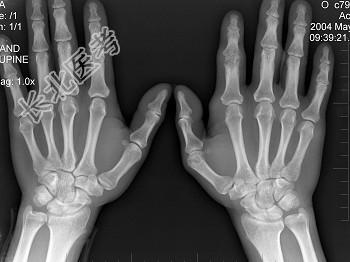

- 单项选择题男,19岁, 双手肿痛2年,晨僵, 结合图像,最可能诊断是 ( )

A、痛风

B、强直性脊柱炎

C、类风湿关节炎

D、退行性关节炎

E、未见异常